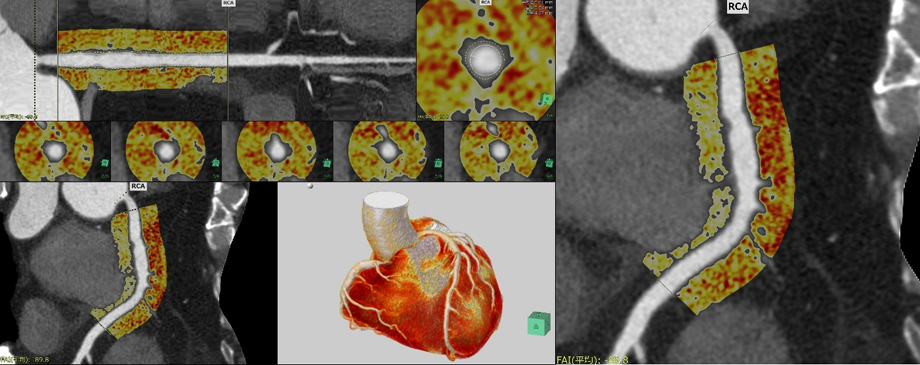

頭部領域や循環器領域、呼吸器領域のアプリケーションにおいても、脳区域解析での正常脳*3との比較や冠動脈解析(CT)内での冠動脈脂肪組織濃度(Fat Attenuation Index: FAI)などの評価指標に新たに対応しました。主な機能は以下の通りである。

心臓の動きを補完してより滑らかな4D画像表現を行うことができる「心臓4Dビューア」を新たにラインアップする。非剛体位置合わせの補完技術により、拍動する心臓の4DCT画像から滑らかな4D画像表現が可能である。また、冠動脈解析(CT)内の機能として、血管周囲の炎症の指標として近年関心が高まっている冠動脈脂肪組織濃度(FAI)の計測機能*5を追加する。循環器領域のご要望に応える機能を搭載し、医療の質向上に貢献する。